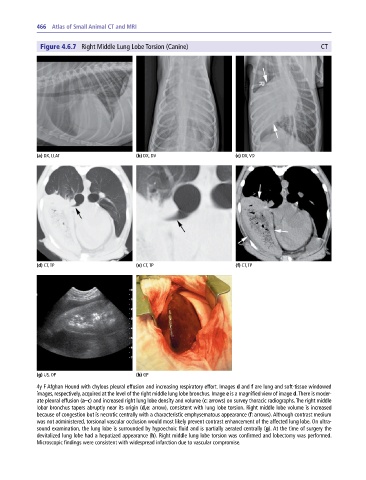

Figure 4.6.7 Right Middle Lung Lobe Torsion (Canine) CT

4y F Afghan Hound with chylous pleural effusion and increasing respiratory effort. Images d and f are lung and soft‐tissue windowed

images, respectively, acquired at the level of the right middle lung lobe bronchus. Image e is a magnified view of image d. There is moder-

ate pleural effusion (a–c) and increased right lung lobe density and volume (c: arrows) on survey thoracic radiographs. The right middle

lobar bronchus tapers abruptly near its origin (d,e: arrow), consistent with lung lobe torsion. Right middle lobe volume is increased

because of congestion but is necrotic centrally with a characteristic emphysematous appearance (f: arrows). Although contrast medium

was not administered, torsional vascular occlusion would most likely prevent contrast enhancement of the affected lung lobe. On ultra-

sound examination, the lung lobe is surrounded by hypoechoic fluid and is partially aerated centrally (g). At the time of surgery the

devitalized lung lobe had a hepatized appearance (h). Right middle lung lobe torsion was confirmed and lobectomy was performed.

Microscopic findings were consistent with widespread infarction due to vascular compromise.